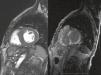

Late gadolinium enhancement (LGE) cardiac magnetic resonance imaging (MRI) is very useful in distinguishing between myocardial infarction, in which the enhancement is typically subendocardial, and myocarditis, in which it is subepicardial (Figure 1). In addition, various patterns have been described with different cardiomyopathies, in some cases enabling a specific diagnosis without invasive workup and risk stratification.1 Cardiac amyloidosis was previously thought to be present only when systemic amyloidosis was patently manifest. This has proved not to be the case, with cardiac MRI detecting increasing numbers of cases in patients with diastolic heart failure in whom cardiac involvement may be the first or sole manifestation. The pattern of LGE commonly found in cardiac amyloidosis is a global subendocardial enhancement with different contrast kinetics, the ventricular cavities showing no signal at all (Figures 2–6) compared to myocarditis and acute myocardial infarction, in which there is an intracavitary gray signal (Figure 1). Of 10 patients referred after echocardiography raised the suspicion of a cardiomyopathy, five were diagnosed with cardiac amyloidosis, two had images not suggestive of amyloidosis and were subsequently found to have Fabry's disease (Figure 7), and the other three probably had concentric left ventricular hypertrophy due to hypertension.